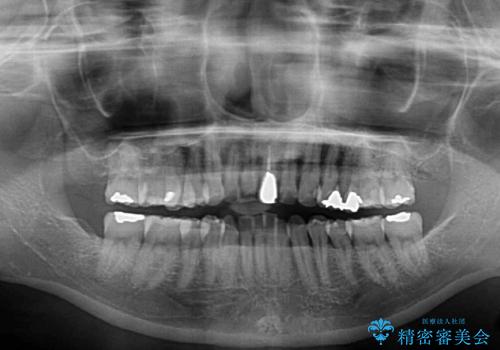

- 前歯のデコボコと変色した前歯を気にして来院された患者様です。

抜歯矯正により口元を引っ込めることも検討しましたが、特に口元の突出感は気になっていないとのことで、非抜歯にてワイヤー装置で矯正治療を行うこととしました。

気になっていた前歯の変色も、矯正治療後にオールセラミッククラウンにて補綴治療を行うこととしました。

舌の突出癖により治療期間中に開咬となり、治療が長引きましたが、口元も治療前よりも引っ込めることができ、すっきりとした仕上がりとなりました。